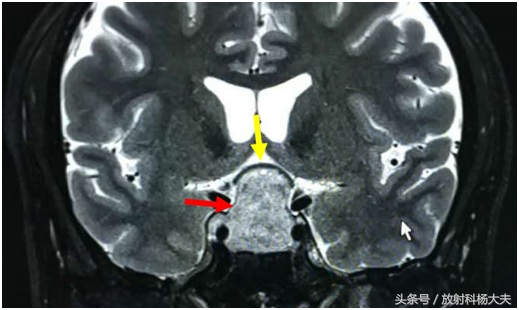

上图是一个垂体周围结构正面观(冠状位)示意图,红圈圈内是垂体,两侧的邻居是海绵窦和颈内动脉(绿圈圈),楼上住着视交叉(黄圈圈)。

当垂体瘤宝宝长大,江湖人称“垂体大腺瘤”,它是这个样子的(如上图红箭所指),健硕的它会向上顶起楼上的视交叉(相当于视神经的十字路口),所以较大的垂体瘤会引起视力损害。